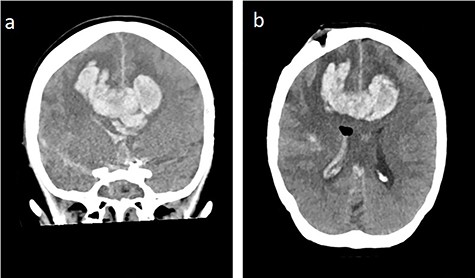

Massive progress of SAH axial cCT at the level of (a) prepontine cistern (arrow) and (b) pentagonal cistern (arrow)

On the next day (Day 9 post-op), the patient suffered from acute and devastating headaches, with screaming and enuresis. An emergency computed tomography (CT) was carried out and displayed a prepontine and retroclival subarachnoid hemorrhage (Hunt & Hess Grade I), (Fig. 2). For further evaluation, a digital subtraction angiography (DSA) was conducted, and it showed a pseudoaneurysm of ophthalmic1/supraclinoid2/C23 part of the left ICA, which was directly treated by a flow diverter (Derivo®—4,5/20), with remaining rest flow (Fig. 3). The patient was transferred to the ICU, transcranial doppler sonography was performed and revealed normal flow. In the following course, the patient suffered from Terson’s syndrome and hyponatremia due to SIADH, but after clinical improvement, was transferred back to normal station after 10 days of post-operative monitoring. Furthermore, the patient was plagued with cephalgia and nausea, which could not be compensated with analgetics and antiemetics. On the 20th post-operative day after the epileptic seizure with postictal vigilance reduction, an emergency CTA was conducted showing progressive SAH (Fig. 4) and a growing pseudoaneurysm as well as generalized vasospasm with posthemorrhagic hydrocephalus. For an emergency CSF diversion, an external ventricle drain was placed. The repeated DSA showed a growing false aneurysm which was treated with two additional flow diverters (2× Derivo®—4,5/20) as well as coiling (HydroSoft™ 2/3 and 2× 1,5/2) by endoleak (Fig. 5). The vasospasms were treated by an intraarterial spasmolysis (Fig. 6).